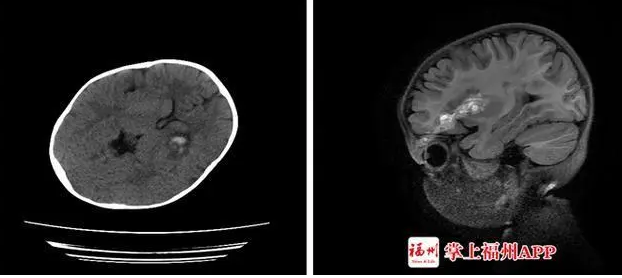

福建一女童小文在獨自玩這個文具時,支撐桿的接口突然斷開,小文不慎往前跌倒,桿子從她的左眼刺進去,孩子血流不止,疼得大哭。家人趕緊把小文送到醫院。醫生發現,這根塑料桿有筷子般粗,插入了小文的左眼。CT檢查顯示,異物已進入顱內,導致顱內出血。全身麻醉后,神經外科醫生幫小文拔出了桿子,觀察一天后,她的狀況穩定,才轉院繼續治療。

福建另一3歲女童小美在家玩回彈軟軸乒乓球。不久,客廳傳來嚎啕大哭聲,小美媽媽聞訊趕來,只看到玩具上的不銹鋼軟軸已插入小美左眼上方。父母帶著小美到醫院治療。接診專家介紹,軟軸刺入造成了小美開放性顱腦損傷、顱內少量血腫、左眼眶上壁骨折伴左眼眶周圍軟組織挫裂傷。醫生說:“萬幸不銹鋼軟軸只是從眼球邊上擦過,沒造成眼球破裂。但還是出現了玻璃體積血,孩子后期視力可能會受影響。”